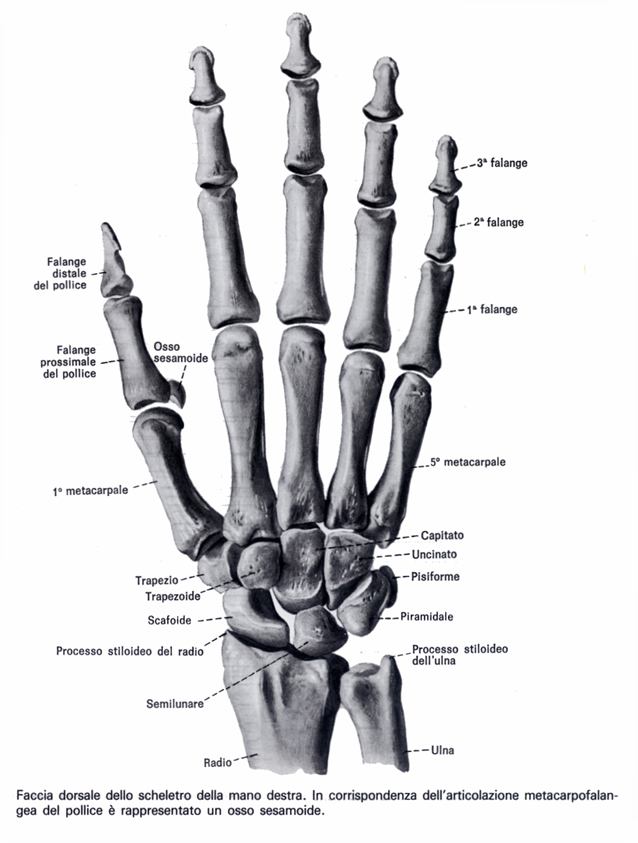

Vengono qui illustrate le tecniche chirurgiche di ostesintesi per la frattura del metacarpo e le fratture multiple dei metacarpi. Nei radiogrammi eseguiti non evidenza di franche alterazioni a focolaio in atto. La frattura del pugile corrisponde alla frattura sottocapitale del quinto metacarpo. Rivalba, nel frontale con il tir vettura distrutta: Complicanze tardive delle fratture della mano. Tutore frattura 5 metacarpo in vendita on line a prezzi imbattibili su ausilium. Infine, in presenza di una frattura. Pagesbusinessesmedical & healthdoctororthopedistmerola ortopediavideosfrattura 5 metacarpo prima della vacanza.il mare è assicurato. Oggi inavvertitamente in casa, mentre chiudevo la finestra ho sbattuto la mano contro la finestra, niente di tremendo ma per un po' mi ha fatto male. Dopo diagnosi frattura testa v metacarpo mano dx (caduta accidentale), mi viene applicato apparecchio gessato con immobilizzazione delle 4 dita, con pollice separato e gomito mobile. Alla rimozione dopo 40 giorni,il paziente presenta rigidità a tutta la mano, in particolare al 4° e 5° dito. Cause e fattori di rischio. Prova a trovare tutore frattura 5 metacarpo in questa pagina, oppure utilizza il motore di ricerca: Il trattamento di una frattura del metacarpo dipende dalla gravità dell'infortunio. Anch'io,tra i vari altri danni,mi son rotto il v° metacarpo in bici,frattura riparata con una vite in titanio,peraltro messa male da un amico carissimo! Alla rimozione, la mano risultava oltremodo gonfia, di colorito un po' più scuro del normale, calda al tatto e. Deformità rotazionale dovuta a una frattura interessante la mano.